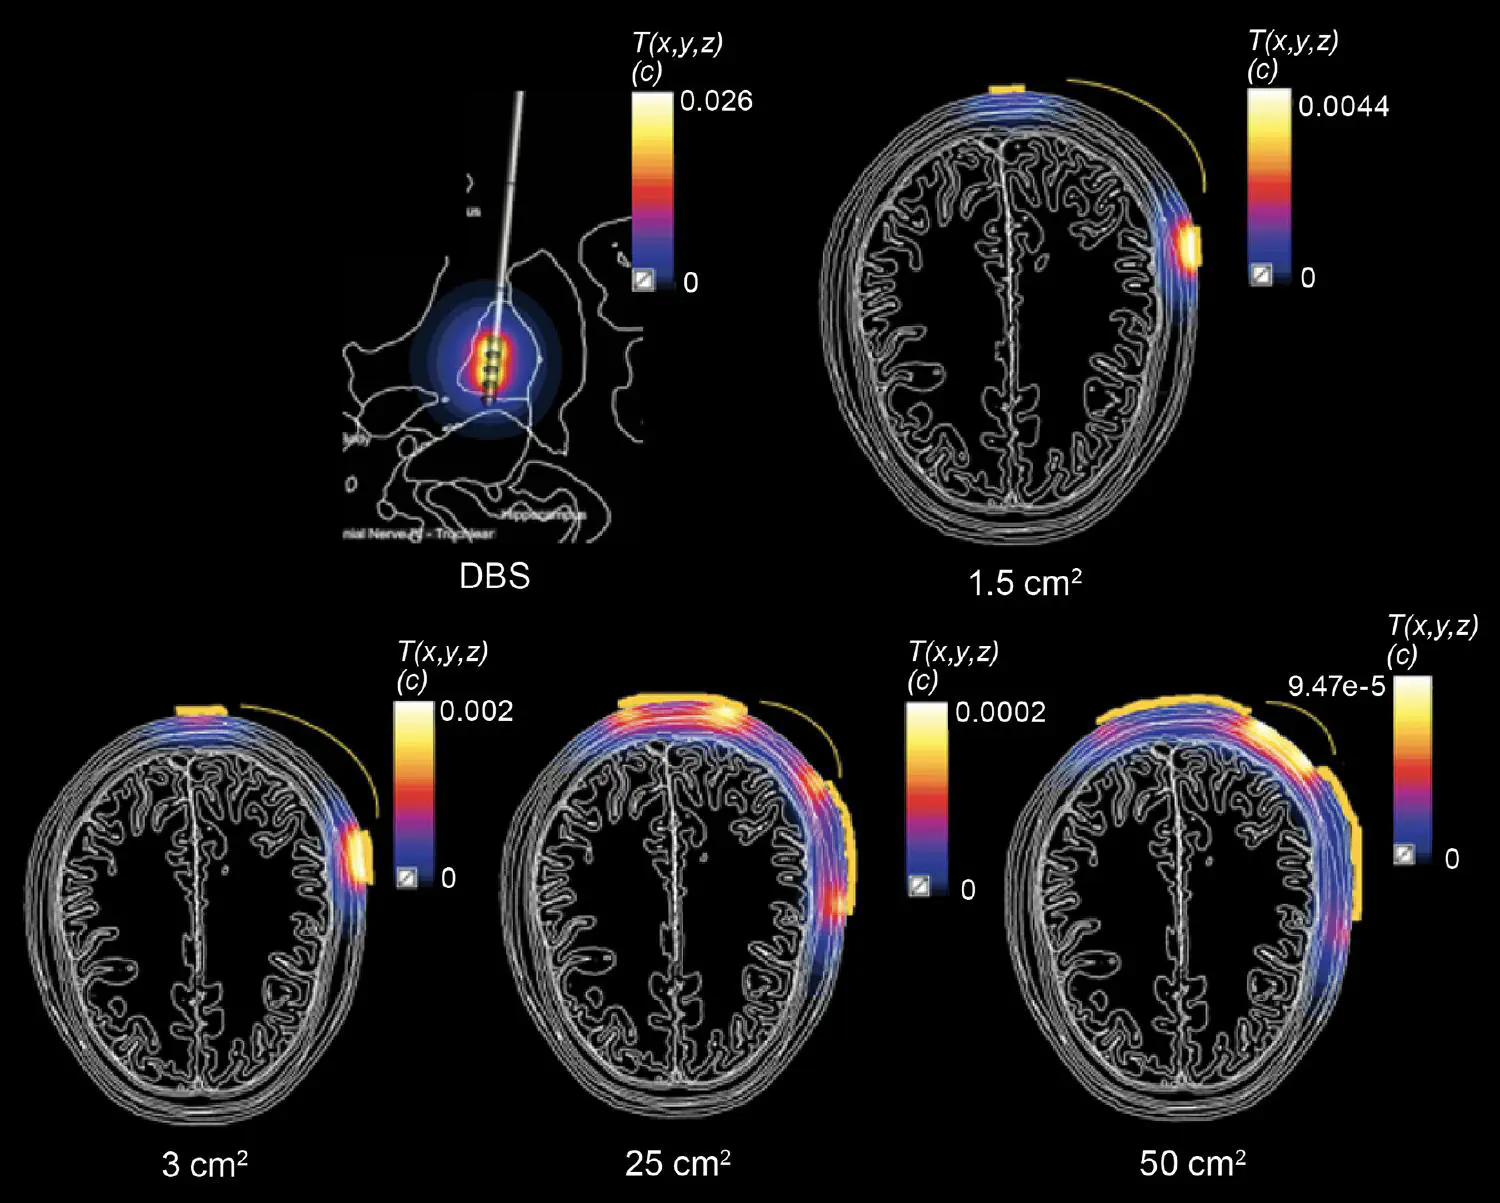

The two-part investigation of TI stimulation safety represents the first systematic effort to establish quantitative safety guidelines for this emerging technology. In TI stimulation, unlike in conventional brain stimulation, two high-frequency electric (E-)fields are applied through scalp electrodes at slightly different frequencies (e.g., 10.00 kHz and 10.01 kHz). While these frequencies are themselves too high to directly stimulate neurons, their interaction creates a low-frequency – in this case 10 Hz – modulation envelope that can influence neural activity at targeted locations deep in the brain. Using advanced computational modeling, the IT’IS team systematically simulated various NIBS exposure scenarios, including TI stimulation, transcranial alternating current stimulation (tACS), and deep brain stimulation (DBS), in a detailed model of the head and brain. By matching field exposure magnitudes across the three stimulation modalities, they calculated TI stimulation parameters that produce conditions known to be safe for tACS and DBS and used these to establish thresholds for the safe application of TI stimulation.

Proposed safety thresholds for TI stimulation by exposure metric (3 cm2 electrodes)2. TI stimulation can be safely used to apply currents of up to 7 mA at frequencies below 2.5 kHz. At frequencies above 2.5 kHz, safe current levels increase linearly with frequency. To avoid unsafe brain tissue heating, no more than 14 mA should be applied at any frequency.

Notably, TI stimulation allows for significantly higher thresholds compared to conventional stimulation methods due to reduced skin sensations at higher frequencies. Also, temperature increases remain well below critical thresholds, with brain tissue heating limited to 0.2°C even at the maximum recommended current. Skin heating stays well below the limits of 2°C set by the U.S. Food and Drug Administration (FDA), ensuring effective blinding conditions and enhancing comfort in experimental and clinical settings. Moreover, TI stimulation permits increased E-field focality compared to conventional stimulation, allowing the targeting of deep brain regions with minimal activation of overlying cortical areas.

Comparison of TIS and transcranial electrical stimulation (tES). Comparison between conventional single tES (left) and total TI stimulation high frequency E-field exposure (center), as well as the corresponding low-frequency TI stimulation modulation magnitude distribution (right). The total TI stimulation carrier frequency E-field map (center) shows the maximal high-frequency field magnitude achieved for in-phase, constructive interference.

Simulated steady-state temperature increase distributions for DBS and tES. Input current of 1 mA, bipolar electrode configuration (top-left) with various electrode sizes. Heating is principally localized near the electrodes, such that brain heating is minimal for tES. In all cases, heating is well below published thresholds for direct tissue damage.